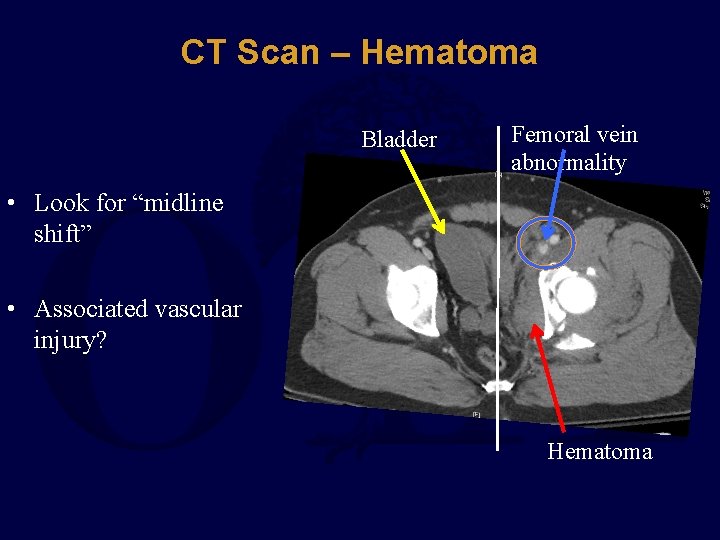

CT Scan – Hematoma Bladder Femoral vein abnormality • Look for “midline shift” • Associated vascular injury? Hematoma